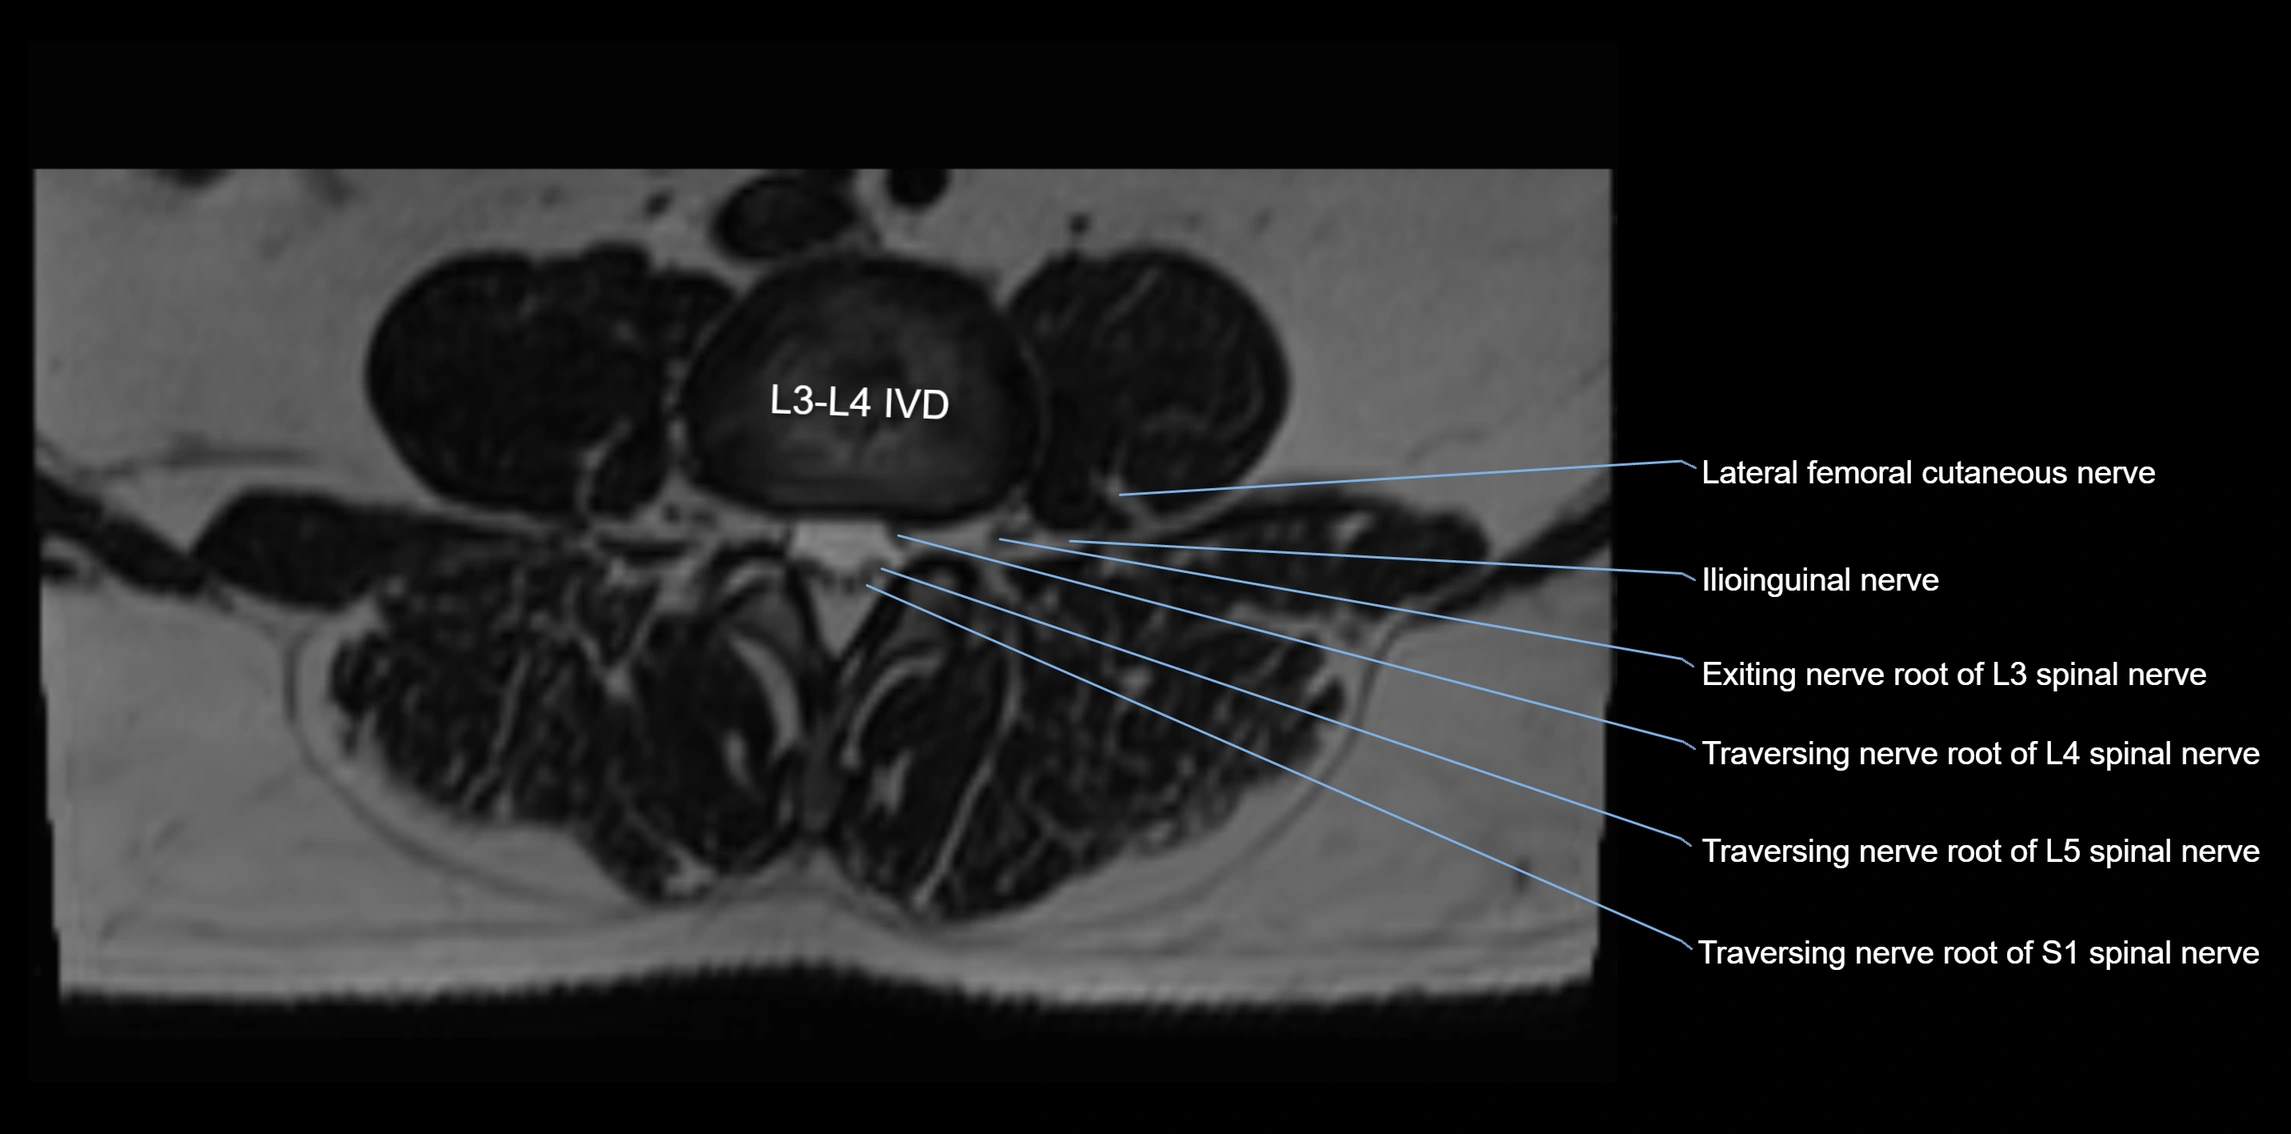

MRI image

image